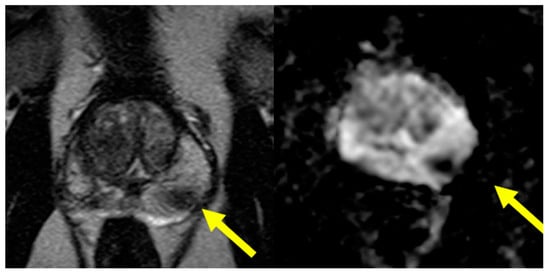

4.2. mpMRI–TRUS Fusion